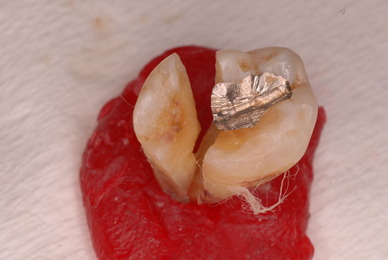

神経が死んでしまった歯は脆いのです。

重症の歯周病で削って上の歯とぶつからないようにしていた歯ですが

いつの間にか神経が死に歯の中が腐っていたようです。

それでヒビが入り割れてしまいました。